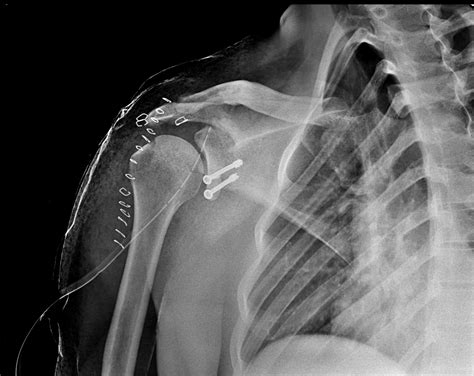

• Arthroscopic Surgery: Minimally invasive surgery to repair the fracture and stabilize the shoulder joint.

• Open Surgery: More invasive procedure to address severe fractures or complex injuries.

• Bone Grafting: In some cases, bone grafting may be necessary to fill the defect caused by the fracture.

• Rehabilitation: Intensive physical therapy to regain strength and mobility in the shoulder.